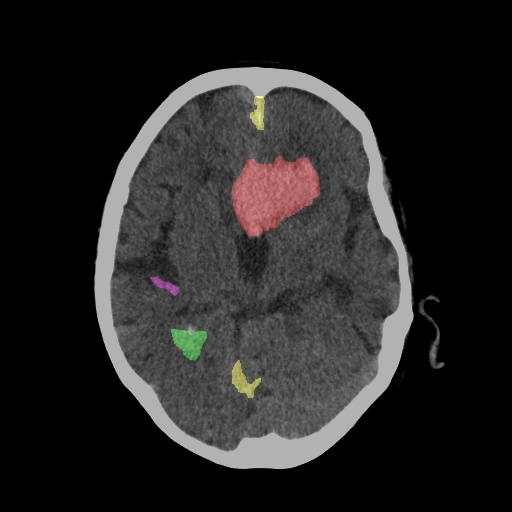

CT Scan After Diagnosis with Segmentation

Hemorrhage Segmentation

Segmentation & Volumetry

Precisely segments the hemorrhage area to calculate its volume, a critical biomarker for patient prognosis.